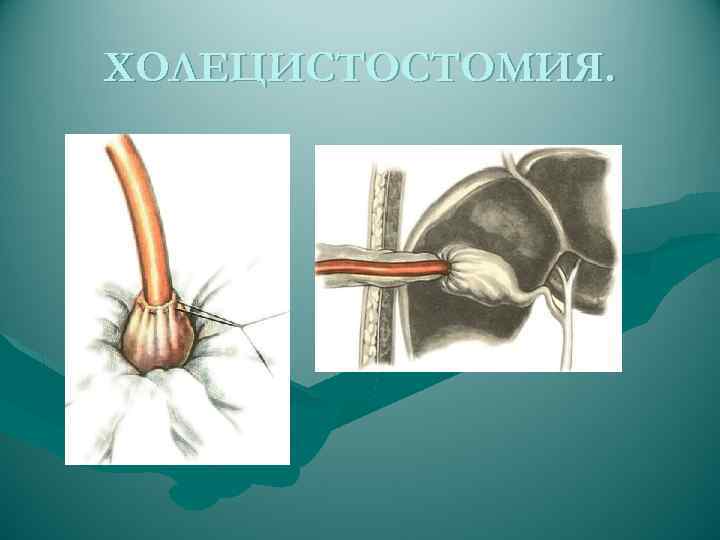

ХОЛЕЦИСТОСТОМИЯ.

ХОЛЕЦИСТОСТОМИЯ.

ХОЛЕЦИСТОСТОМИЯ.

ХОЛЕЦИСТОСТОМИЯ.